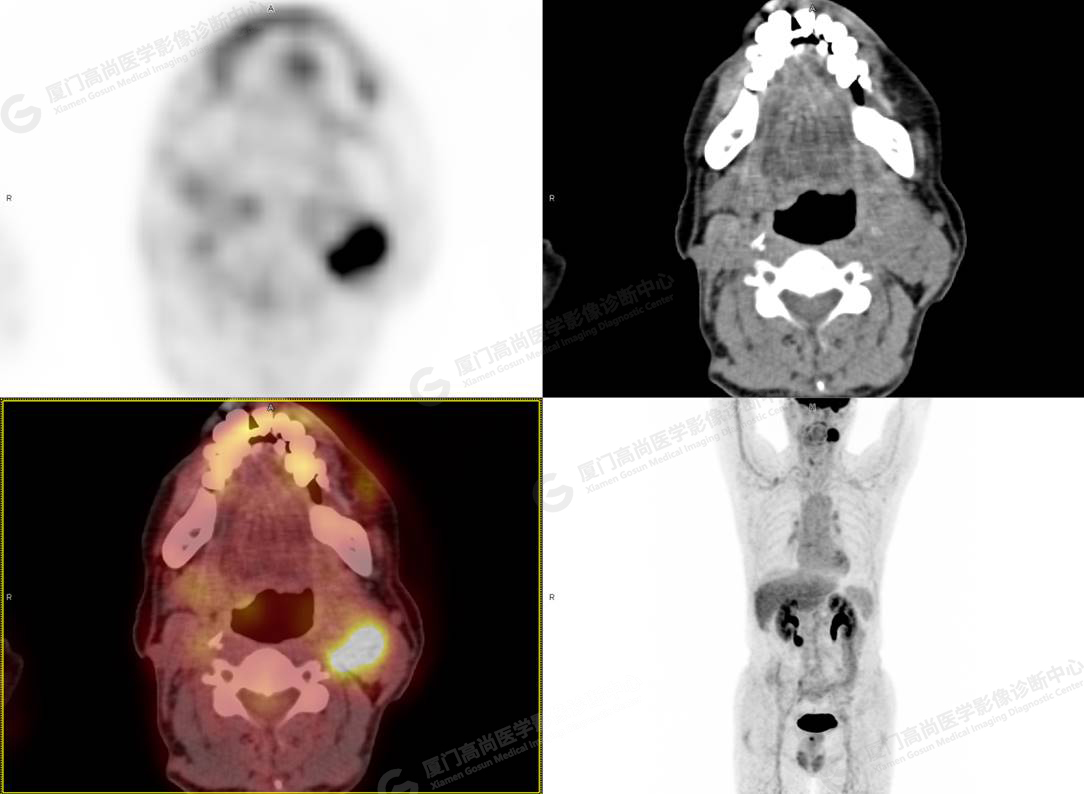

PET/CT影像圖

圖3

PET/CT所見:左側頸部(II區(qū))見腫大淋巴結,大小約2.5cm×2.3cm,其內密度不均,邊界尚清,放射性攝取異常增高,早期SUVmax 11.5,延時SUVmax 14.5。

影像診斷: 左側頸部(II區(qū))腫大淋巴結,代謝異常增高,考慮腫瘤性病變可能性大(淋巴瘤?轉移瘤?),建議病理學檢查明確。

病理診斷:(左頸部結節(jié))副神經節(jié)瘤。